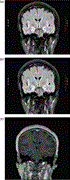

Delayed central nervous system manifestation of Chikungunya virus with magnetic resonance T2 weighted imaging high signal changes—a case report

Preci L Hamilton and Garth Cruickshank

Journal of Surgical Case Reports, Volume 2018, Issue 6, June 2018, rjy134, https://doi.org/10.1093/jscr/rjy134